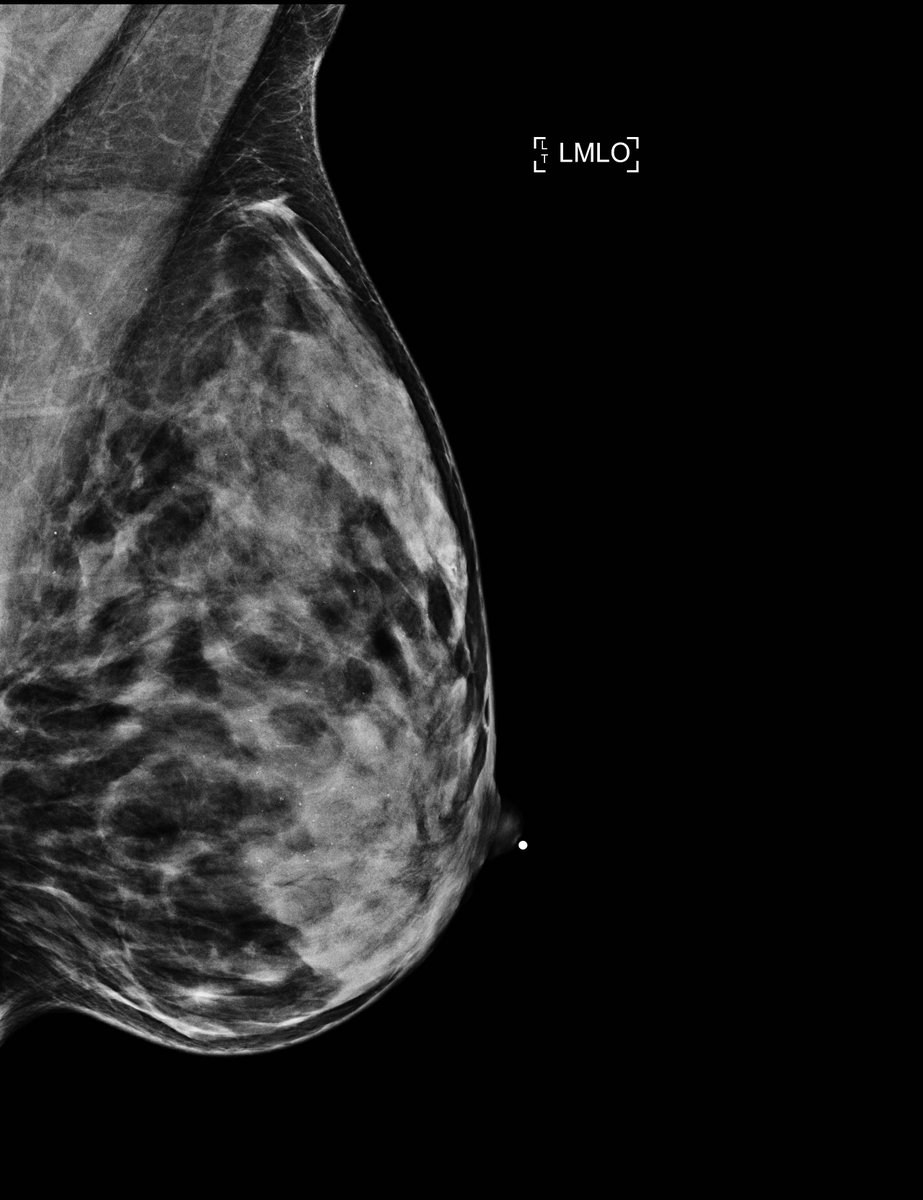

@kjgeras and@NanWu__, researchers at@nyuschoolofmed and@NYUDataScience, have created an AI diagnostic tool that's helping doctors detect breast cancer with more accuracy. Learn more about this important work on the new episode of "NYU Brainiacs": http://spr.ly/60151esTz pic.twitter.com/pGyfMRK20BHvala. Twitter će to iskoristiti za poboljšanje vaše vremenske crte. PoništiPoništi -

Researchers at the NYU Center for Data Science and the NYU School of Medicine have created an AI diagnostic tool that's helping doctors detect breast cancer with more accuracy. Follow this link to check out more: https://www.youtube.com/watch?time_continue=1&v=urJ7QEdhP_U&feature=emb_logo …pic.twitter.com/aHvfHEU8sE